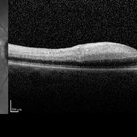

68-year-old woman with decreased central vision over past few months following viral illness.

68-year-old woman with decreased central vision over past few months following viral illness